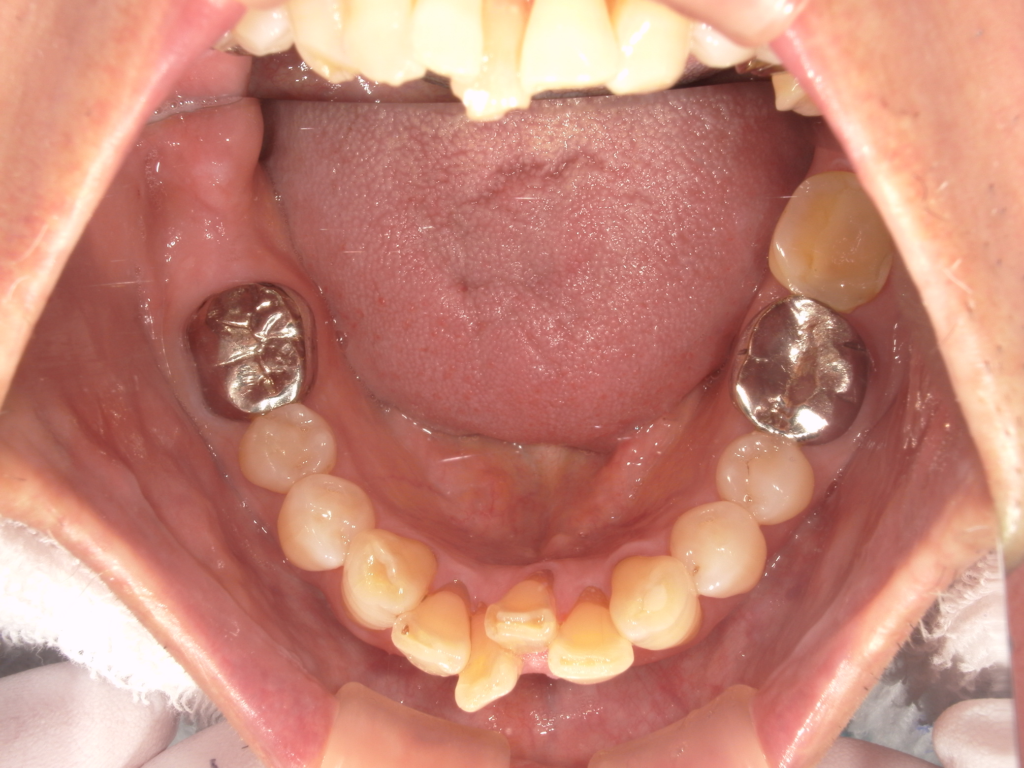

Y様インプラント実例 #44

左の上下の奥歯をインプラントで治療しています。

左下の奥歯は歯を抜くのと同時にインプラントの埋め込みを行っています。

被せものは上下、セラミックスで作っています。

治療前

治療後